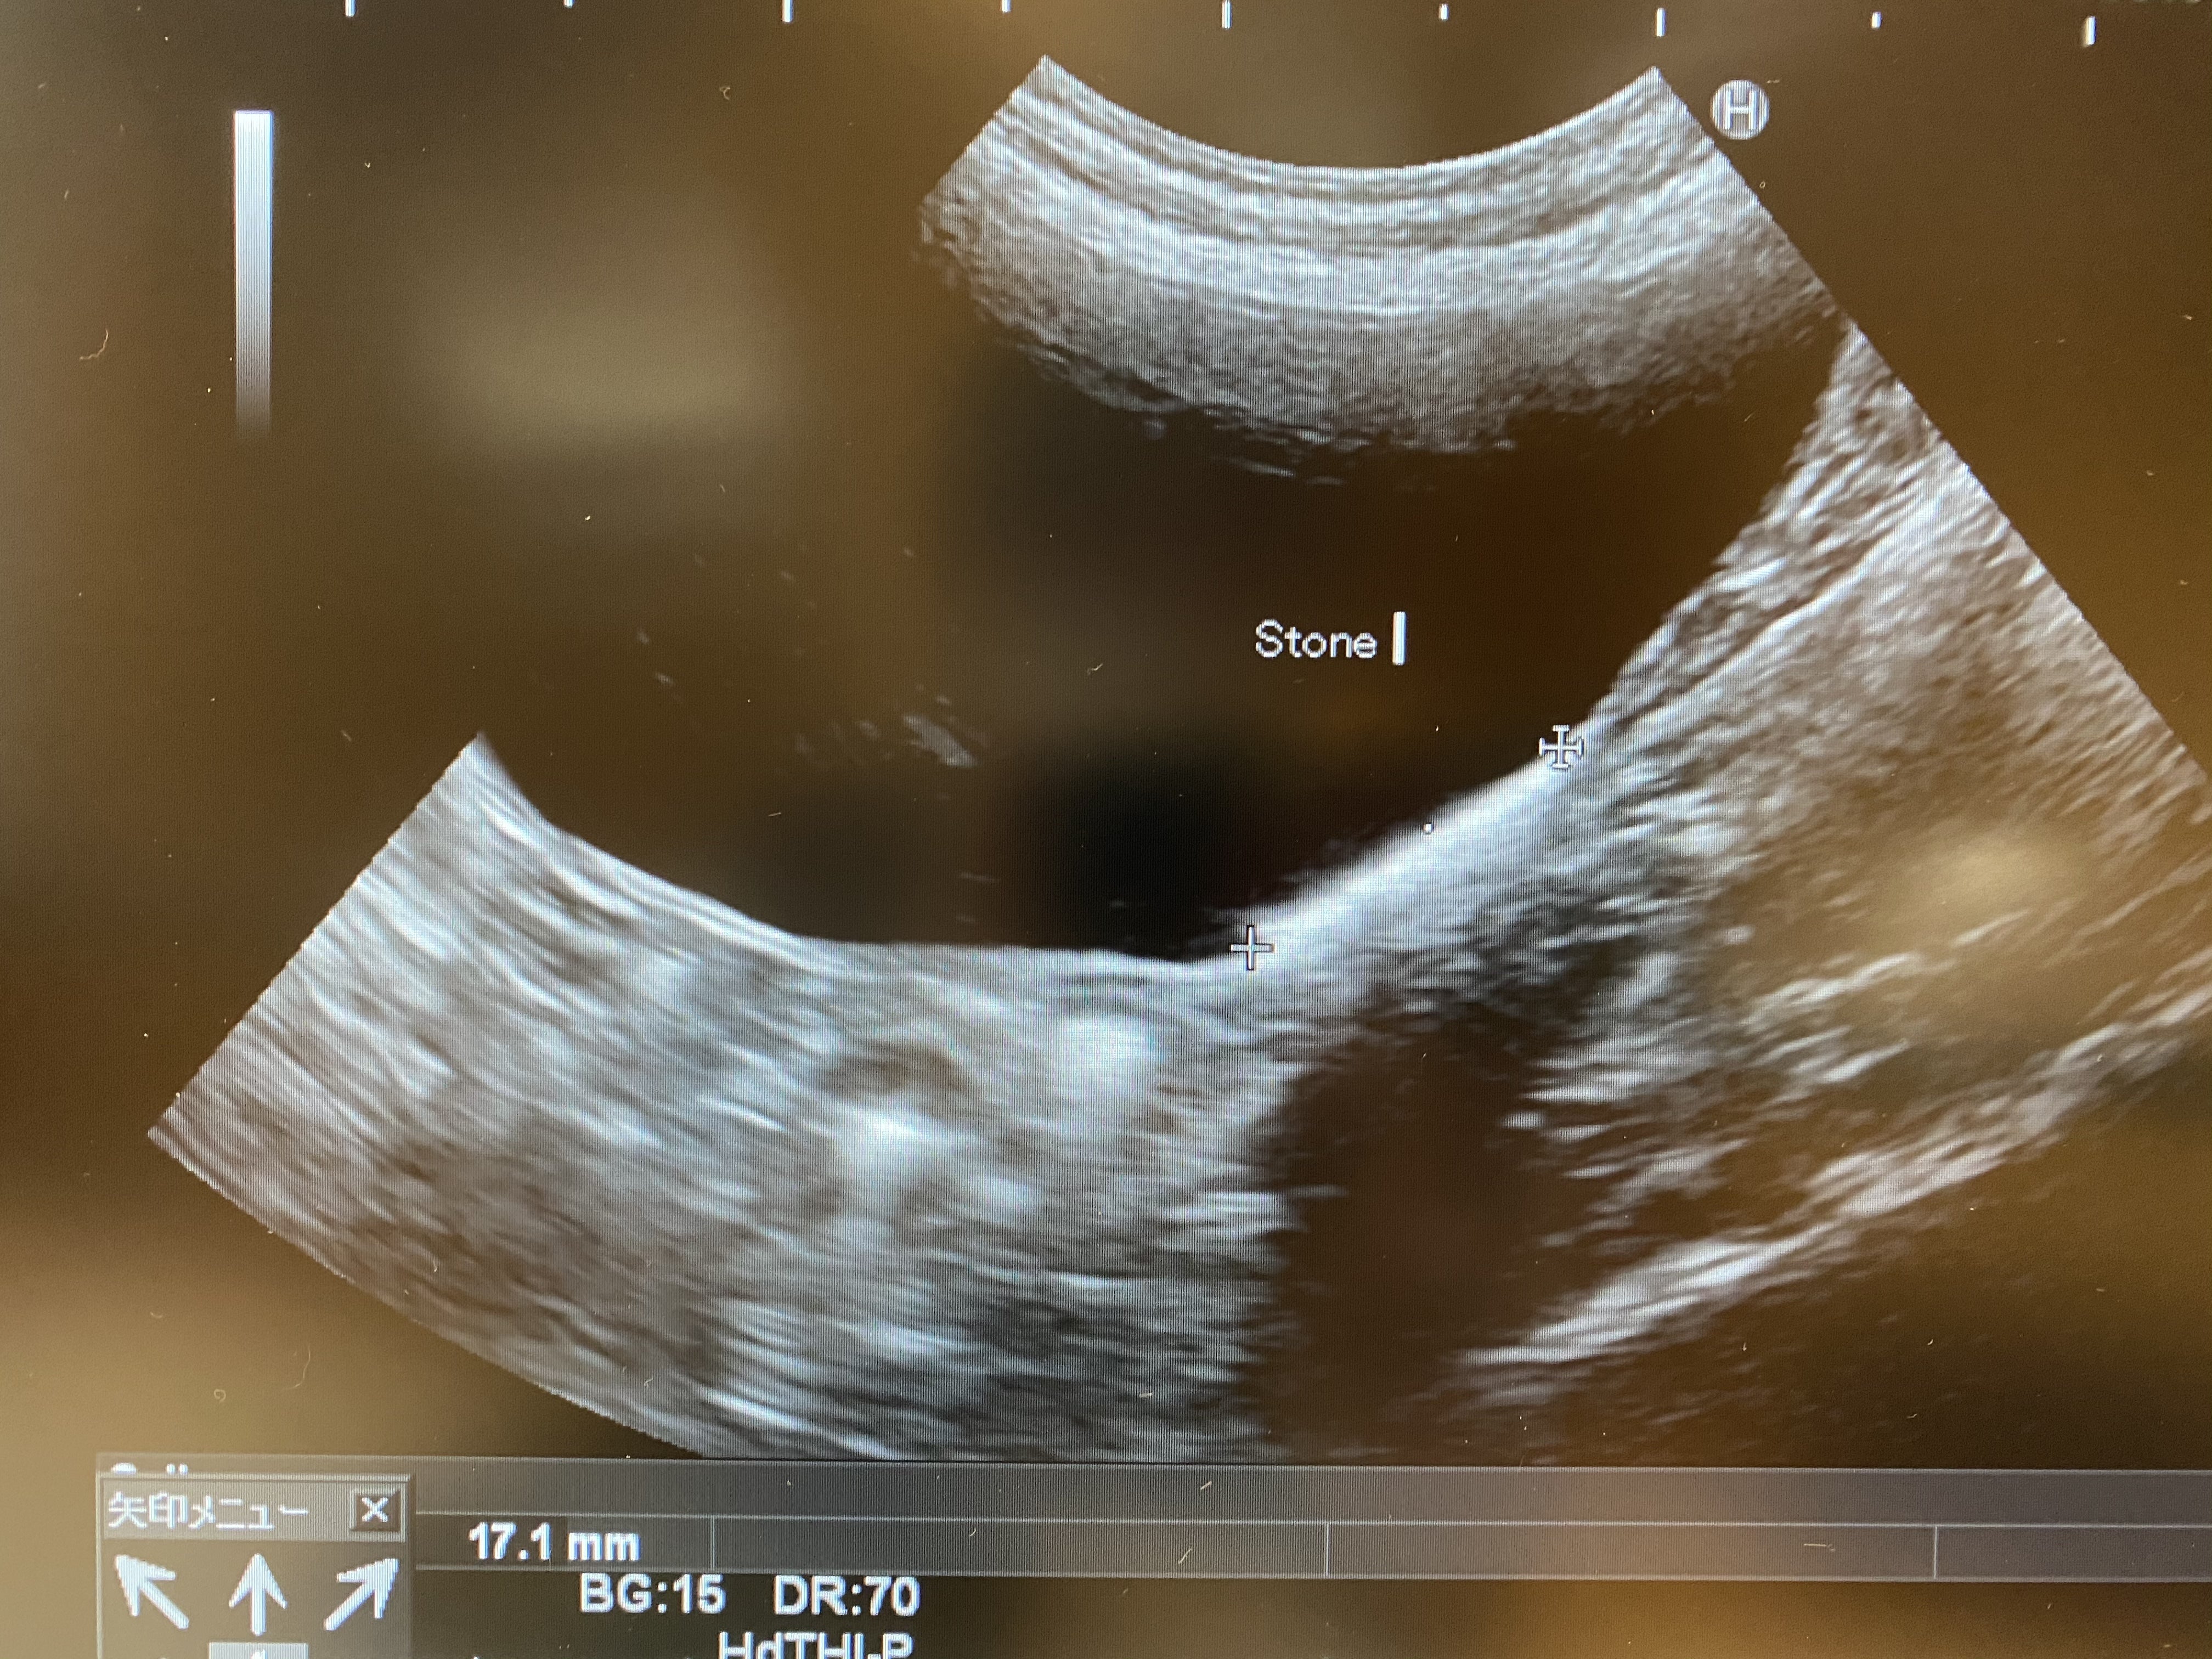

その他、手術に支障のある大きな問題は無かったのですが、ひとつだけ心配なのがエコー検査で見つかった尿結石です。

Stoneと書いてある下の白く厚くなっているところに石の壁ができているようです

膀胱の壁に直径17.1mmほどの範囲で細かい砂利のような石が薄く溜まっているようで、それが手術で崩れたりして尿管に落ちてこないことを祈るのみです…

とても小さく薄くあるだけなので、今すぐ何か症状が出たり手術が必要な程ではないようです。

結石の原因となるミネラル系のご飯やおやつは取ったりしていないので、体質だろうとのことでした。

これに関しては定期的な経過観察をして、様子を見ましょうと話をしました。